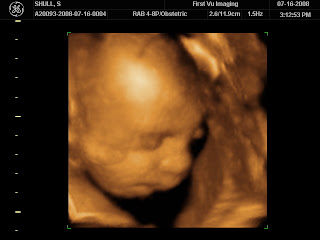

Look at our baby!

Thanks to Andrea, Andrew and I went to have 4-D photos taken of our baby. It was such a fun experience. The technician was careful to only snap photos from the waist up so that we didn’t find out the gender. The baby behaved very well during the session. It had a fascination with one of its feet. It had the little foot all the way up by the head playing with it and wiggling it around. It’s hard to believe that in 2 months, this precious little baby will be at home with us.